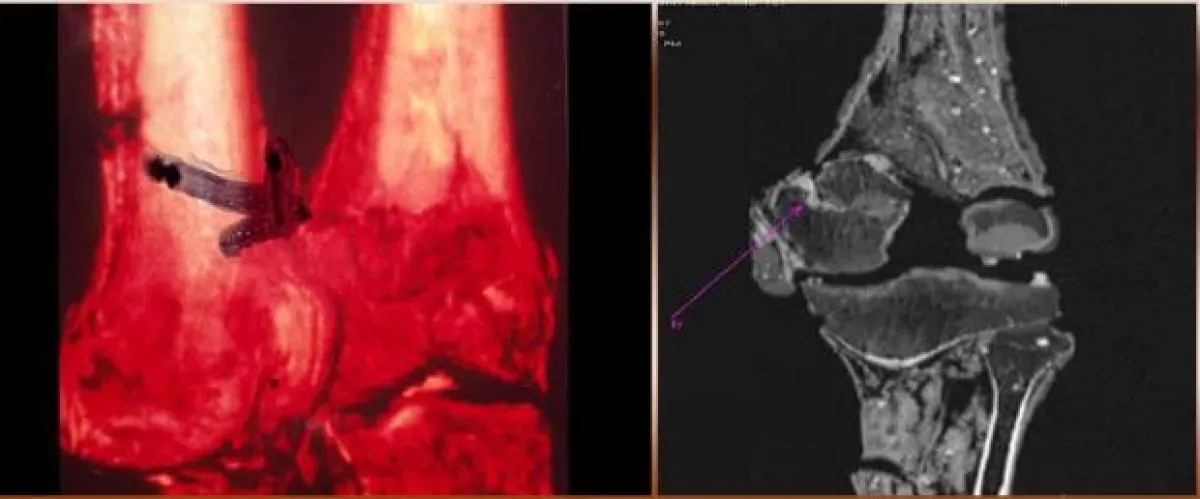

أوضح فحص بالأشعة المقطعية، الذي أجرى عام 2005، قطع عظم الفخذ الأيسر قبل أيام قليلة من الموت.

بينما وجد تحليل آخر في عام 2013 أنه تم سحقه على جانب واحد من جسده، وتأثير السحق يبدو في الحوض والأضلاع.